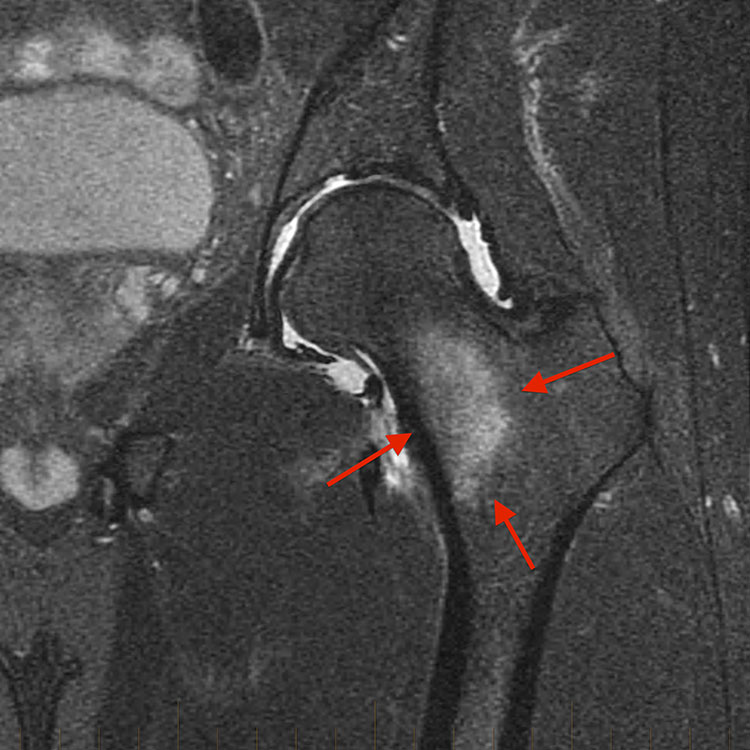

• 척추분리증 진단의 주요 선택 양상 Modality이며, 척추관절간부 부위에서 골수 부종이 관찰 될 수 있음.

• 척추분리증의 골절선 유무 및 완전성을 추가로 확인하기 위해 표적 CT가 필요할 수 있다.

• x-ray로 쉽게 시각화 되지 않는 주상골, pars interarticularis 척추관절간부와 같은 뼈의 피질 골절을 시각화하는 데 필요할 수 있다.

• pars interarticularis 척추분리증의 만성, 완전 피로골절은 x-ray로 감지 될 수 있지만, 급성 피로골절은 감지되지 않는다.